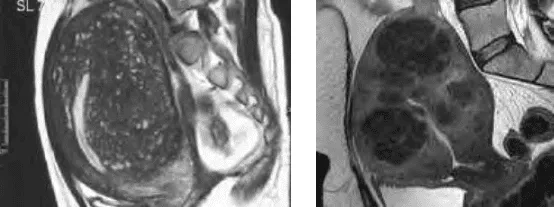

MRI: Phân biệt adenomyosis (JZ dày > 40%, tín hiệu hỗn hợp) với u xơ (tín hiệu đồng nhất giảm trên T2W).

Hình ảnh “MRI của adenomyosis và u xơ tử cung”.